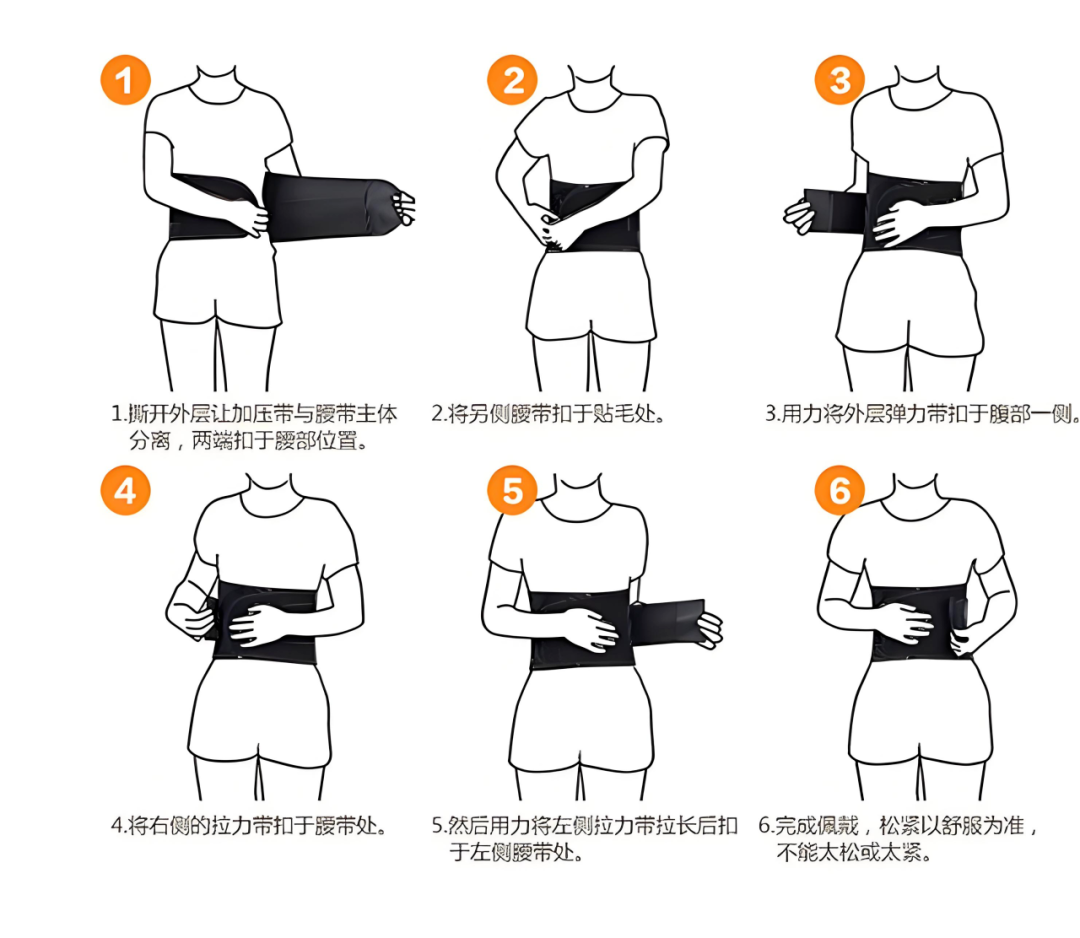

3.下床活动:通常在术后2小时,如果患者疼痛缓解且生命体征稳定,可以在医护人员指导下佩戴腰围或支具,逐步下床活动。初次下床时,应由医护人员或家属协助,避免跌倒。

2.保持正确体态:坐、站、走路时都要佩戴腰围,时刻保持脊柱挺直,不要长时间保持一个姿势,尤其是弯腰、扭转身体的动作要坚决避免。